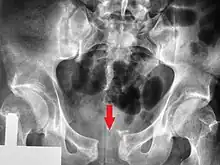

| A pelvic X-ray showing an open book fracture | |

Open book fracture

One specific kind of pelvic fracture is known as an 'open book' fracture. This is often the result of a heavy impact to the groin (pubis), a common motorcycling accident injury. In this kind of injury, the left and right halves of the pelvis are separated at front and rear, the front opening more than the rear, i.e. like an open book that falls to the ground and splits in the middle. Depending on the severity, this may require surgical reconstruction before rehabilitation.[11] Forces from an anterior or posterior direction, like head-on car accidents, usually cause external rotation of the hemipelvis, an “open-book” injury. Open fractures have an increased risk of infection and hemorrhaging from vessel injury, leading to higher mortality.[12]